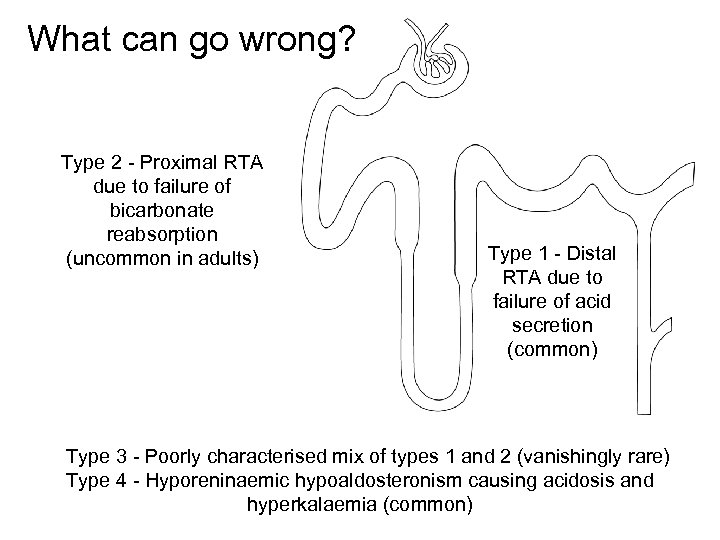

What can go wrong? Type 2 - Proximal RTA due to failure of bicarbonate reabsorption (uncommon in adults) Type 1 - Distal RTA due to failure of acid secretion (common) Type 3 - Poorly characterised mix of types 1 and 2 (vanishingly rare) Type 4 - Hyporeninaemic hypoaldosteronism causing acidosis and hyperkalaemia (common)

What can go wrong? Type 2 - Proximal RTA due to failure of bicarbonate reabsorption (uncommon in adults) Type 1 - Distal RTA due to failure of acid secretion (common) Type 3 - Poorly characterised mix of types 1 and 2 (vanishingly rare) Type 4 - Hyporeninaemic hypoaldosteronism causing acidosis and hyperkalaemia (common)